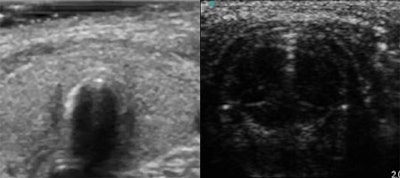

| Ultrasound confirmed the trachea (left) and the glottic plan (right). |

In the second study, Marciniak's group had 30 children (mean age of 48 months) scheduled for surgery under general anesthesia, although patients who met the criteria for difficult intubation were excluded. The same ultrasound placement as the previous study was used, and the probe was moved on the thorax and under the clavicle.

According to the results, the trachea was always identified on sonography by the tracheal rings. Also, the glottic plan was characterized by the visualization of the vocal cords, which moved during respiration. Finally, tracheal intubation provided enhanced shadowing posterior to the tracheal ring.